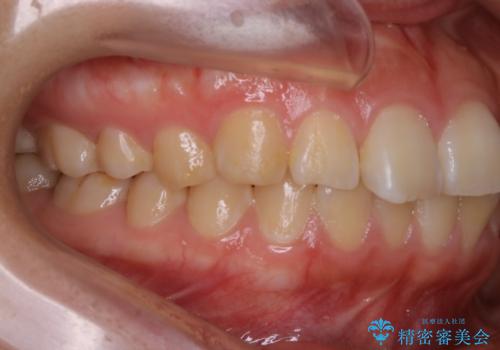

【非抜歯】ガタつきと歯軸を正して長持ちする歯へ

- 歯のガタつきと噛み合わせの改善を主訴に来院されました。

非抜歯で、少量の奥歯の移動と歯列の拡大・IPRを駆使して主訴を改善するための治療計画を立案しました。